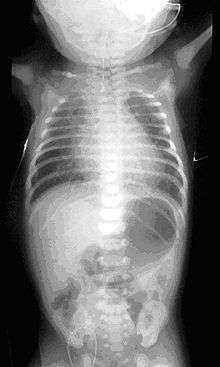

If any of the above signs/symptoms are noticed, a catheter is gently passed into the esophagus to check for resistance. If resistance is noted, other studies will be done to confirm the diagnosis. A catheter can be inserted and will show up as white on a regular x-ray film to demonstrate the blind pouch ending. Sometimes a small amount of barium (chalk-like liquid) is placed through the mouth to diagnose the problems.